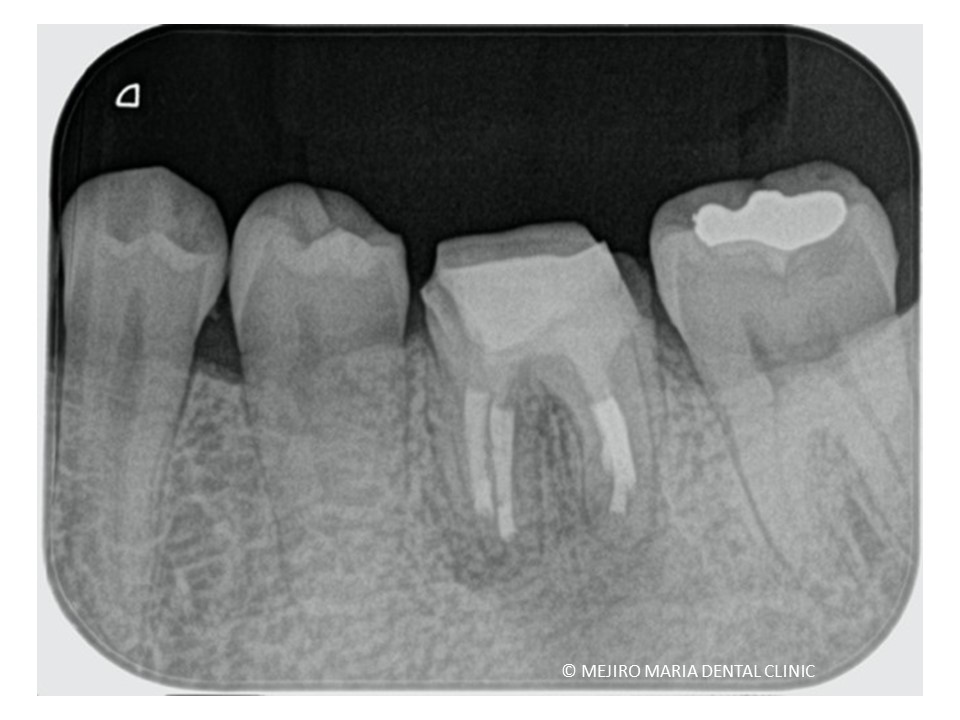

治療詳細

当院にて再根管治療を施すもサイナストラクト(瘻孔・フィステル)の消失は確認できず、予後不良と判断し歯根端切除術を行った。

根管治療は解剖学的に洗浄が困難な場合や根尖孔外感染(細菌が根の外に歯石の様な塊を形成する)の場合など通法の根管治療では治癒に至らない症例があります。

そのような症例に長期的に何度も根管治療を施すことは感染経路の拡大や、歯質の過切削につながり逆に予後を悪くする原因となるのです。このような症例は可及的速やかに歯根端切除術に移行することが重要だと考えます。